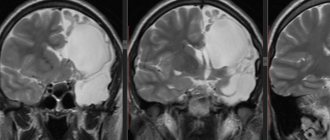

Головной мозг имеет несколько оболочек. Одна из них называется арахноидальной. Пространство под ней (субарахноидальное),